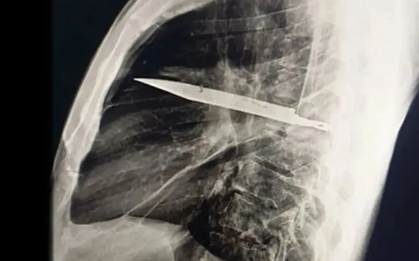

Một trường hợp y khoa gây sốc vừa được ghi nhận tại Tanzania: một người đàn ông 44 tuổi đến bệnh viện vì vùng ngực dưới núm vú phải chảy dịch mủ kéo dài 10 ngày. Bệnh nhân không hề sốt, không khó thở, cũng không có biểu hiện đau đớn nào bất thường.